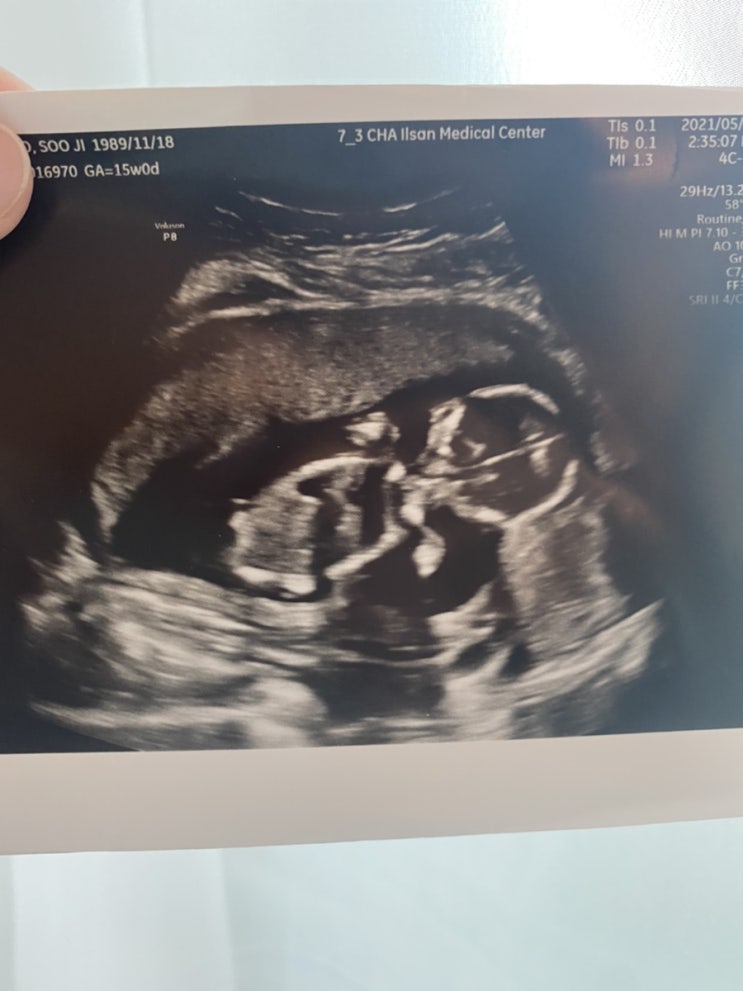

임신 15주: 질통증(밑빠짐 통증)으로 병원/ 임신15주 초음파 성별?/임신 두통 철분제 복용시작

임신 15주 증상 질통증(믿빠짐 통증)으로 병원행 임신 15주 초음파 성별?! 임신 투동 철분제 복용 시작 16...